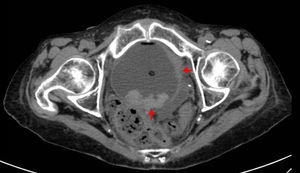

Mujer de 72 años, sin antecedentes reumatológicos de interés, que acudió a la consulta de Reumatología por dolor nocturno y rigidez matutina en manos y pies, de un mes de evolución, acompañados de edema difuso, fóvea e impotencia funcional. No presentaba síndrome constitucional, clínica de arteritis de la temporal, aftas, uveítis o lesiones cutáneas. En la analítica destacaban: velocidad de sedimentación globular de 120mm, proteína C reactiva de 111mg/l y hemoglobina de 8,6mg/dl. El factor reumatoide, los anticuerpos contra péptidos citrulinados y el HLA B27 fueron negativos. No se hallaron alteraciones en el proteinograma, las inmunoglobulinas y la orina de 24 h. El estudio radiológico de manos y pies solo detectó artrosis interfalángica distal de las manos y un aumento de las partes blandas en manos y pies. Con los datos anteriores y aplicando los criterios de Olivo2 fue diagnosticada de síndrome RS3PE. Se inició tratamiento con prednisona (10mg/día) y antiinflamatorios no esteroideos por la noche; tras 4 semanas de escasa mejoría, se añadió hidroxicloroquina (2/día), mejorando progresivamente. A los 3 meses, desapareció la sintomatología y se normalizaron los reactantes de fase aguda. Teniendo en cuenta el posible contexto paraneoplásico, se solicitó una radiografía de tórax, en la que no se detectaron anomalías, y una ecografía abdominal, en la que se halló una tumoración vesical que fue confirmada en la tomografía computarizada toraco-abdominal (fig. 1). Se realizó cistoscopia con toma de biopsias de la lesión. La anatomía patológica informó de un carcinoma de células transicionales con infiltración de la pared muscular y en la gammagrafía ósea no objetivaron metástasis. Desde el punto de vista reumático, la paciente fue respondiendo peor al tratamiento propuesto. A nivel general, el severo y rápido deterioro clínico contraindicó la cistectomía radical y la paciente falleció a los 5 meses del diagnóstico reumatológico.